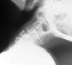

The cervical spine is commonly involved. Often there are multiple vertebral fusions, C2 - C3 fusion, odontoid abnormalities, odontoid absence, and ball and socket occiput-atlanto joint with or without instability.